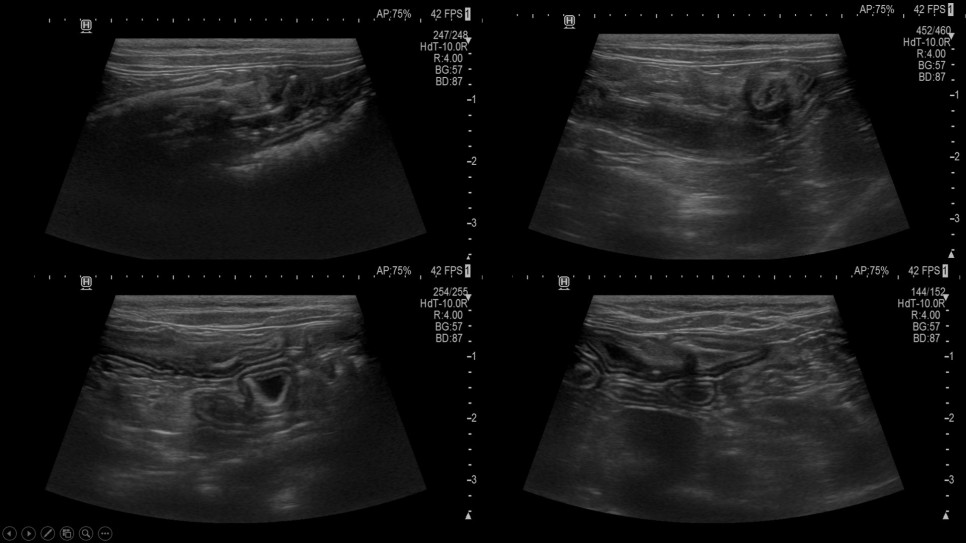

초음파

초음파 검사 결과 횡격막 탈장과 함께 소장 내 선형 이물질이 광범위하게 확인되었으며, 이로 인한 장폐색 소견이 동반되고 있는 것으로 확인되었습니다.구토의 직접적인 원인은 선형 이물질에 의한 장폐색이라고 판단되었으나, 횡격막 탈장에 대한 교정도 필요한 상태라고 판단되어 수술 계획을 위한 CT 검사를 실시했습니다.CT